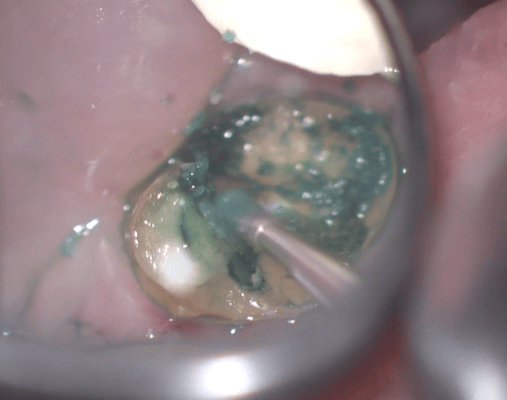

他院では抜歯と診断された歯ですが、それも間違えではありません。しかし、歯肉圧排をしたりすれば、保存できる可能性があることも多くあります。最初の状態ではラバーダム施すことが困難です。虫歯を除去中に歯髄の一部が露出しましたが、隔壁を作製し、防湿ができる環境を作って、歯髄を除去せずに保存できました。

クラウンを外すと、歯肉縁下までの大きな虫歯が確認できます。ラバーダムができないので、簡易防湿を行い、歯肉溝からの浸出液の侵入を防ぎます。隣の歯の間にまたがる虫歯ですが、丁寧に軟化象牙質を除去します。歯髄の露出はありましたが、特殊なセメントで緊密にシール(絆創膏みたいなもの)します。歯髄を除去せずにすみました。